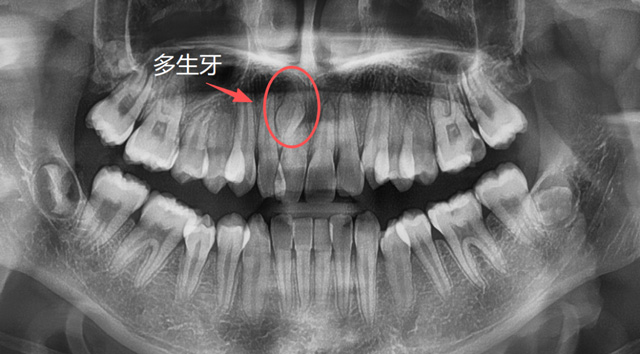

儿童上颌多生牙

建议家长在小朋友处于替牙期的时候,不管有没有牙疼,都找专业的口腔医生进行检查,必要时拍片看一下牙胚的数量有无出入,关注一下牙齿是否按正常的顺序完成了替换,如有异常情况,可以及时干预。

有些人因为牙列拥挤、乳牙滞留或先天发育等原因,恒牙没有在正常的位置萌出,反而往上颌窦、鼻腔等方向生长;称为“异位牙”,还有的牙因为全部或部分埋在了牙槽骨里,无法萌出,称为“阻生牙”,很多智齿就是这样的情况;还有一些超出正常数量的“多生牙”,通常也埋在牙槽骨里无法萌出。